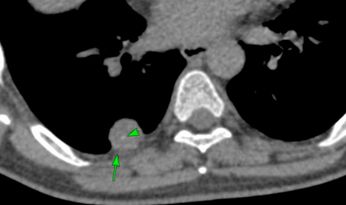

Case of the Day - 099 - Rheumatoid Arthritis Associated Lung Nodules Paid Members Public

When multiple nodules are seen in a patient with RA, it is necessary to rule out infection, neoplasm and associated vasculitis before labeling them as rheumatoid nodules